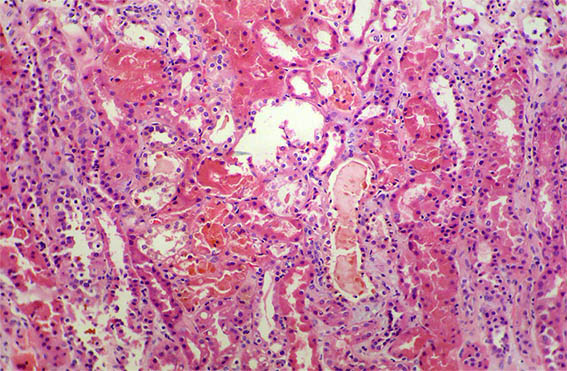

A 40-year-old man presented with severe acute liver failure secondary to hepatitis A virus infection, and acute kidney injury.

More relevant laboratory tests: thrombocytopenia (76,000), hyperbilirubinemia (7.1 mg/dL), transaminitis (1.830 U/L and 2.320 U/L), and elevated INR. Serum creatinine: 5.2 mg/dL, BUN: 78 mg/dL, proteinuria: 100 mg/dL, without microhematuria.

A kidney biopsy was performed. Look at the images.

Figure 1. H&E, X100.